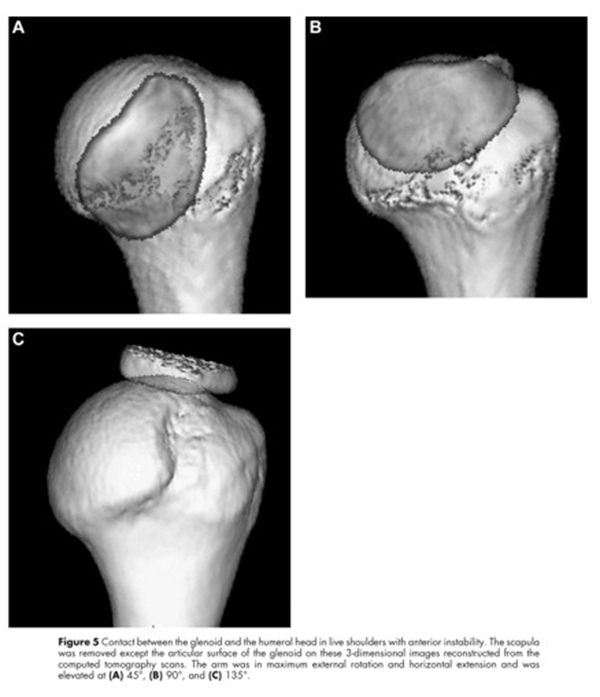

当手臂上举时,肩胛盂与肱骨头的接触区域会从肱骨头的中下部向外上部分转移,这个相互的接触区域就被称为肩胛盂轨迹。接触区域的内侧缘到肩袖止点的内侧缘的距离约为84%肩胛盂的宽度。

图12

当没有肩胛盂骨缺损时,肩胛盂轨迹的宽度占了肩胛盂宽度的84%。当有肩胛盂前缘骨缺损时,应该从这84%的长度中减去骨缺损的宽度,这样才能够获得一个真正的肩胛盂轨迹的宽度。